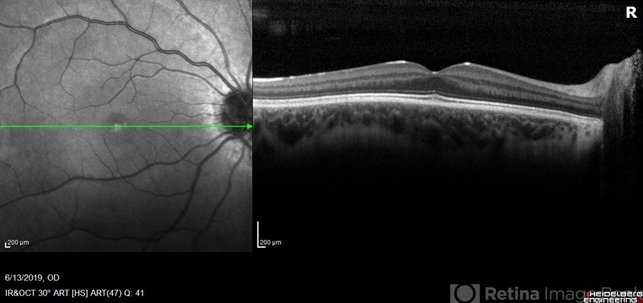

- optical coherence tomography (OCT), congenital stationary night blindness (CSNB), infrared image

- OCT/infrared image showing myopic fundus with normal retinal structure in patient with CACNA1F associated X-linked CSNB (OD).